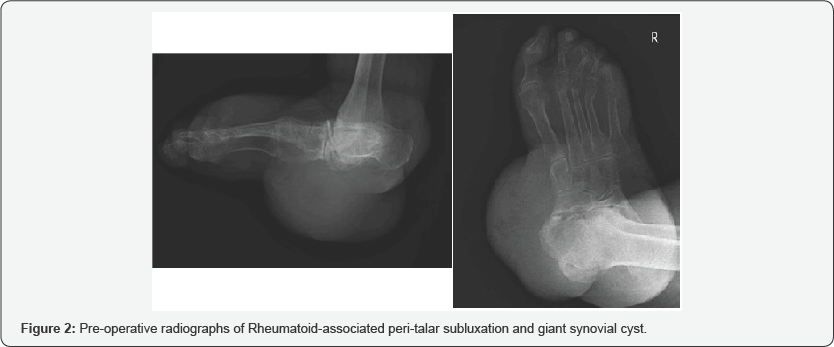

Radiographs were obtained for further evaluation. The plantar rear foot mass was obvious. Rheumatoid rear foot destruction and chronic peri-talar subluxation was severe; shown in Figure 2. An MRI was not possible now since she recently had a pacemaker implanted. Three years earlier, an MRI had been performed (prior to initial surgical excision); images shown in Figure 3. The patient was made aware of the risk for below knee amputation but elected limb salvage. She was consented for surgical excision and biopsy. A longitudinal excision was created along the course of the mass. Dissection was carried down to the deep fascial layer overlaying the giant mass.